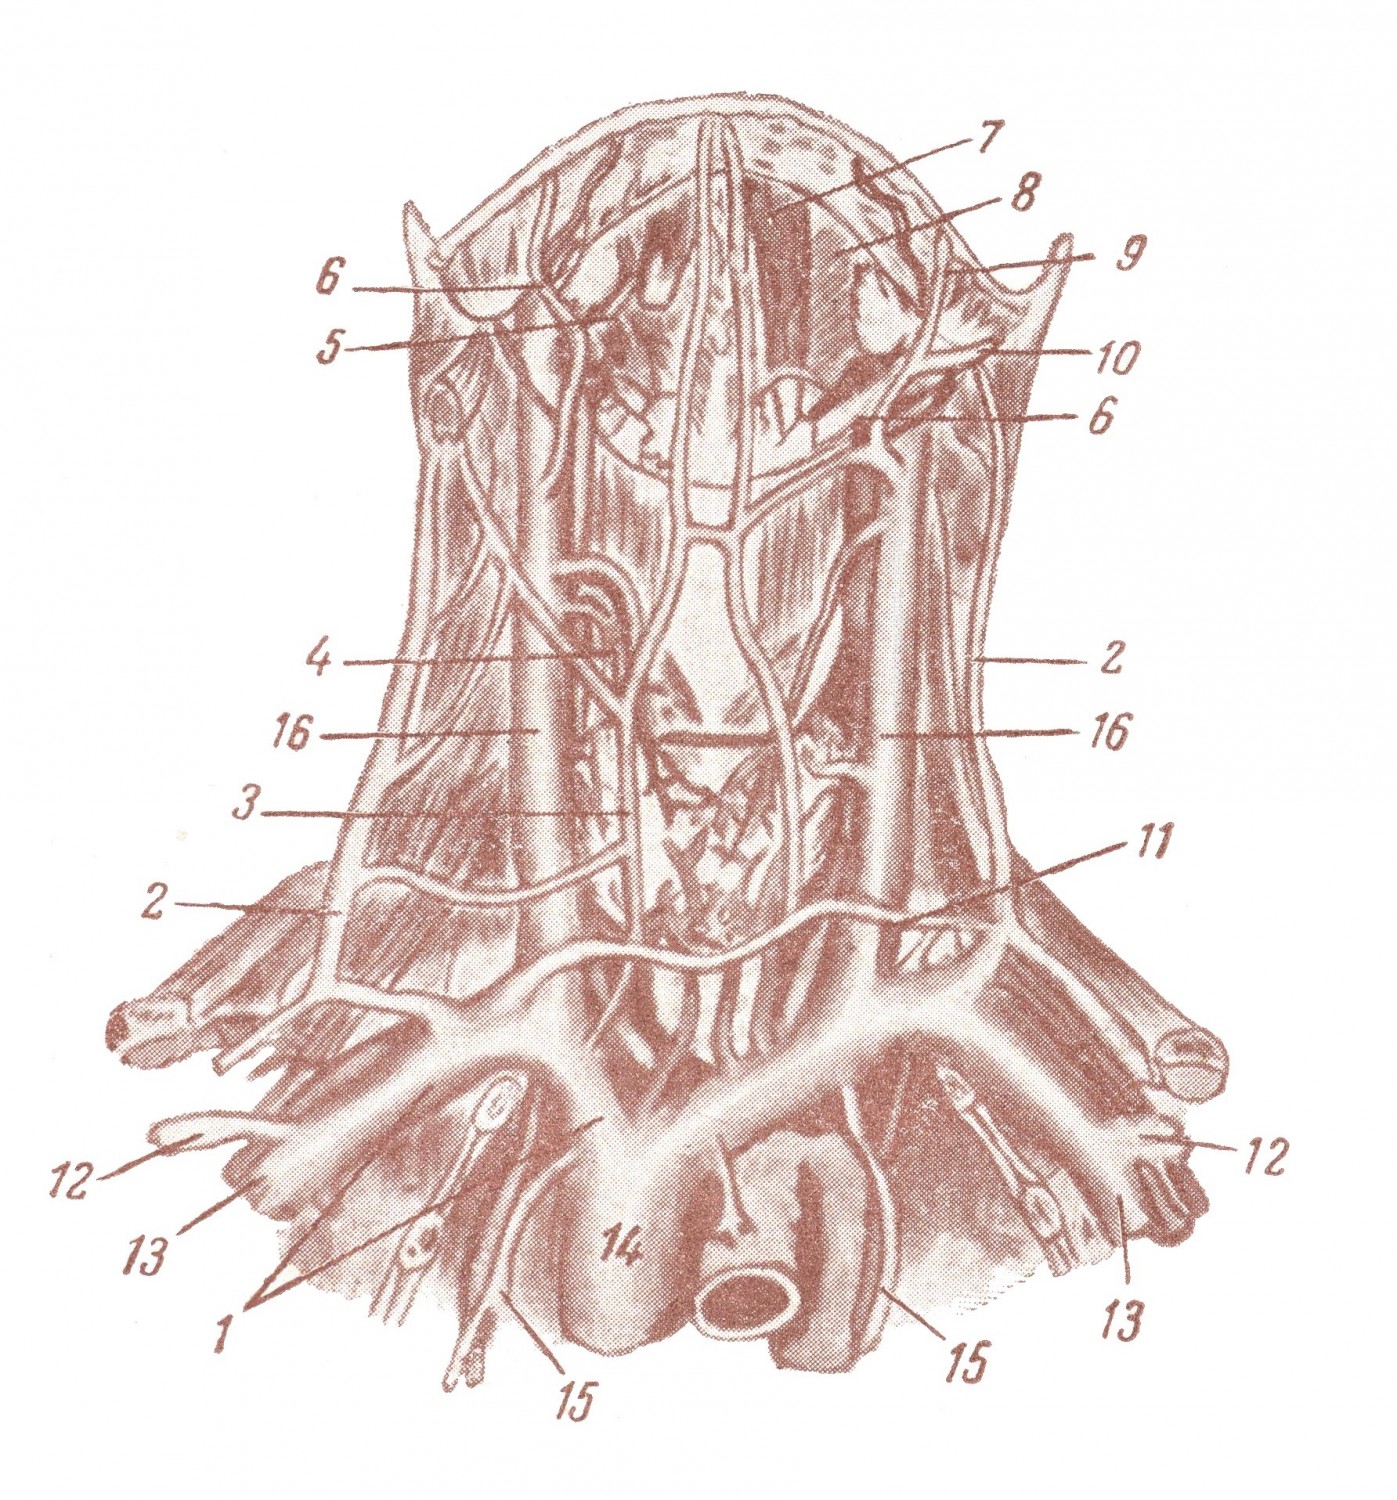

Анатомия внутренней яремной вены: КТ изображения